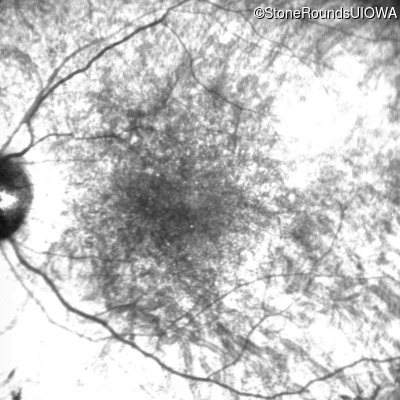

Infrared Fundus Photograph - Right - 10/140 sc

Exemplar